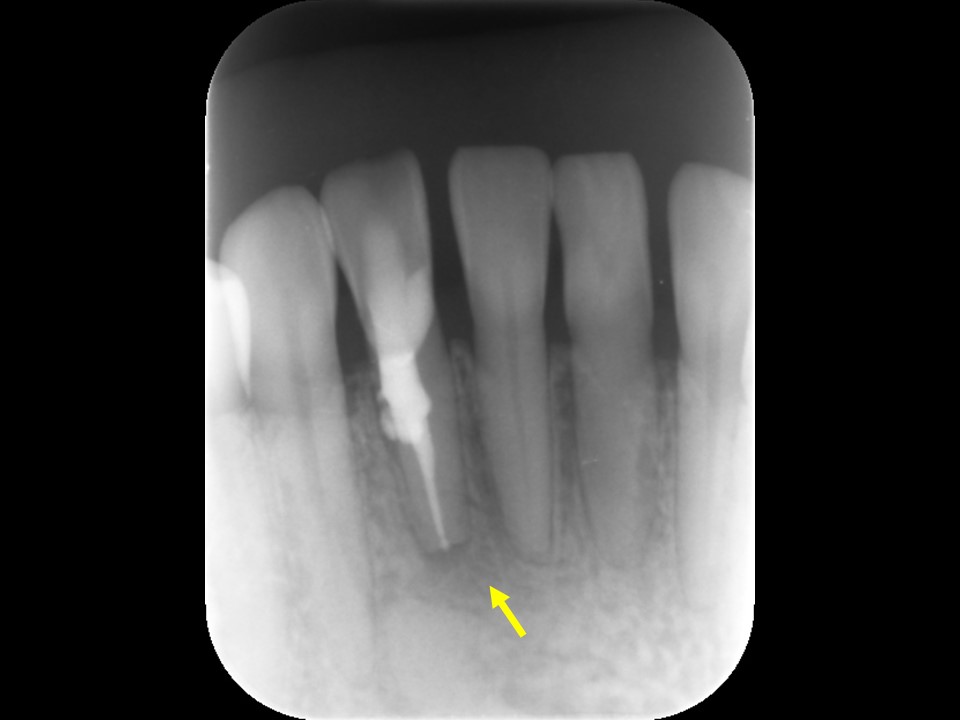

図1、 初診時レントゲン |

図2、初診時CT像 |

![]() |

図1、上顎前歯部の痛みと歯茎の腫れを主訴に来院。根尖部に大きな黒いレントゲン透過像を認める(矢印)。

図2、根尖部は母指頭大の大きな骨吸収像を認める(矢印)。虫歯に継発した歯髄壊死と診断し、精密根管治療を行うこととした。